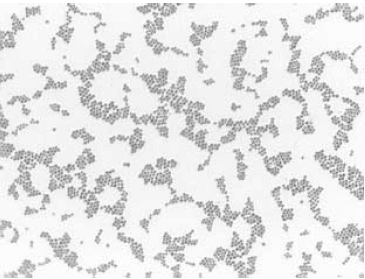

Material recebido em laboratório para análise microbiológica por bacterioscopia, cultura e antibiograma revelou a presença de Staphylococcus sp. O material é proveniente de swab coletado de ferida cirúrgica que apresenta resposta inflamatória intensa e secreção purulenta. Como o objetivo do médico era identificar o foco infeccioso, e havia suspeita de infecção urinária, também foram solicitados EAS e urocultura.

A figura abaixo é compatível com a morfologia do microrganismo identificado na secreção.